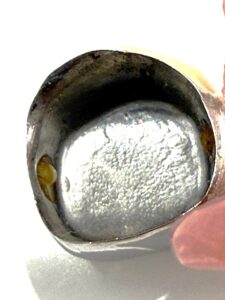

この内冠に合わせて外冠が作られ、外冠の内面にはPEEK(ポリエーテルエーテルケトン)という耐久性の高い樹脂が貼られています。これが維持装置として働きます。